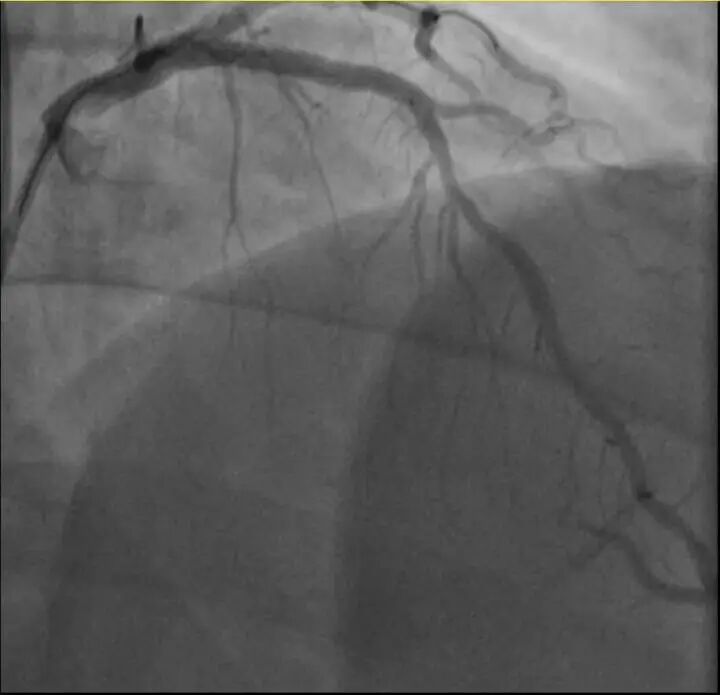

前不久,他带孩子到羽毛球场操练,手痒之下自己也上场,仅10分钟左右,就因心前区剧烈绞痛被送进了急诊。浙江医院心血管内科医师分析,剧烈运动导致这位患者心脏的不稳定斑块破裂,进而造成前降支近段次全闭塞。所幸送医及时,接受紧急介入治疗后,孙先生的身体险情被成功化解。

介入治疗前后影像图